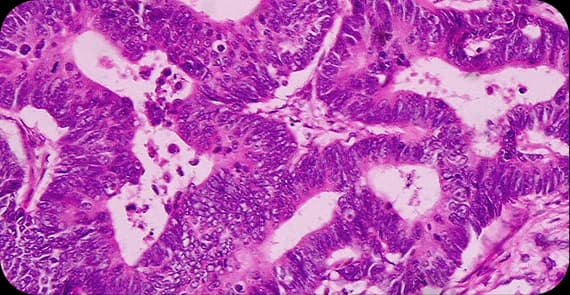

There are different types of prostate cancer depending on the cells from which the tumour arises.

A rare and more aggressive subtype.